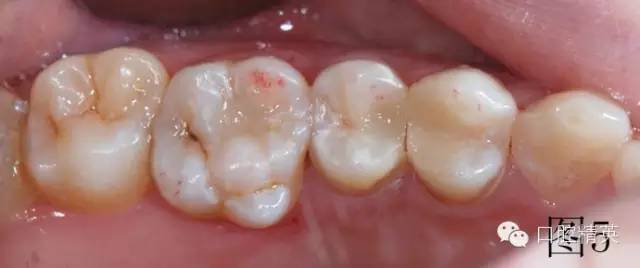

調牙合,圖5中上頜第一磨牙近中頰尖有紅色咬合點,此為牙合干擾點,調磨至沒有,最后拋光。治療結束,邊緣非常密合,患者非常滿意,沒有感到橡皮障任何不舒服的地方,唾液可自行吞咽。